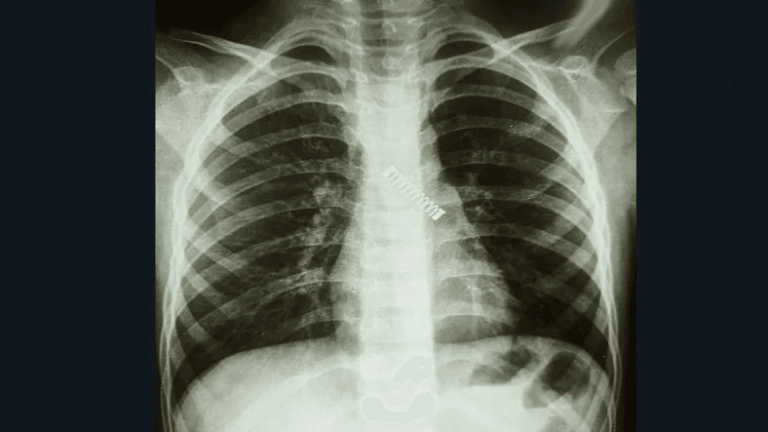

De acuerdo al reporte médico, del Dr. Carlos Morínigo, el niño fue sometido a una placa del tórax, se lo derivó inmediatamente hasta el Ineram y a tempranas horas de este jueves, fue sometido a una complicada cirugía para la extracción del metal del bronquio izquierdo.